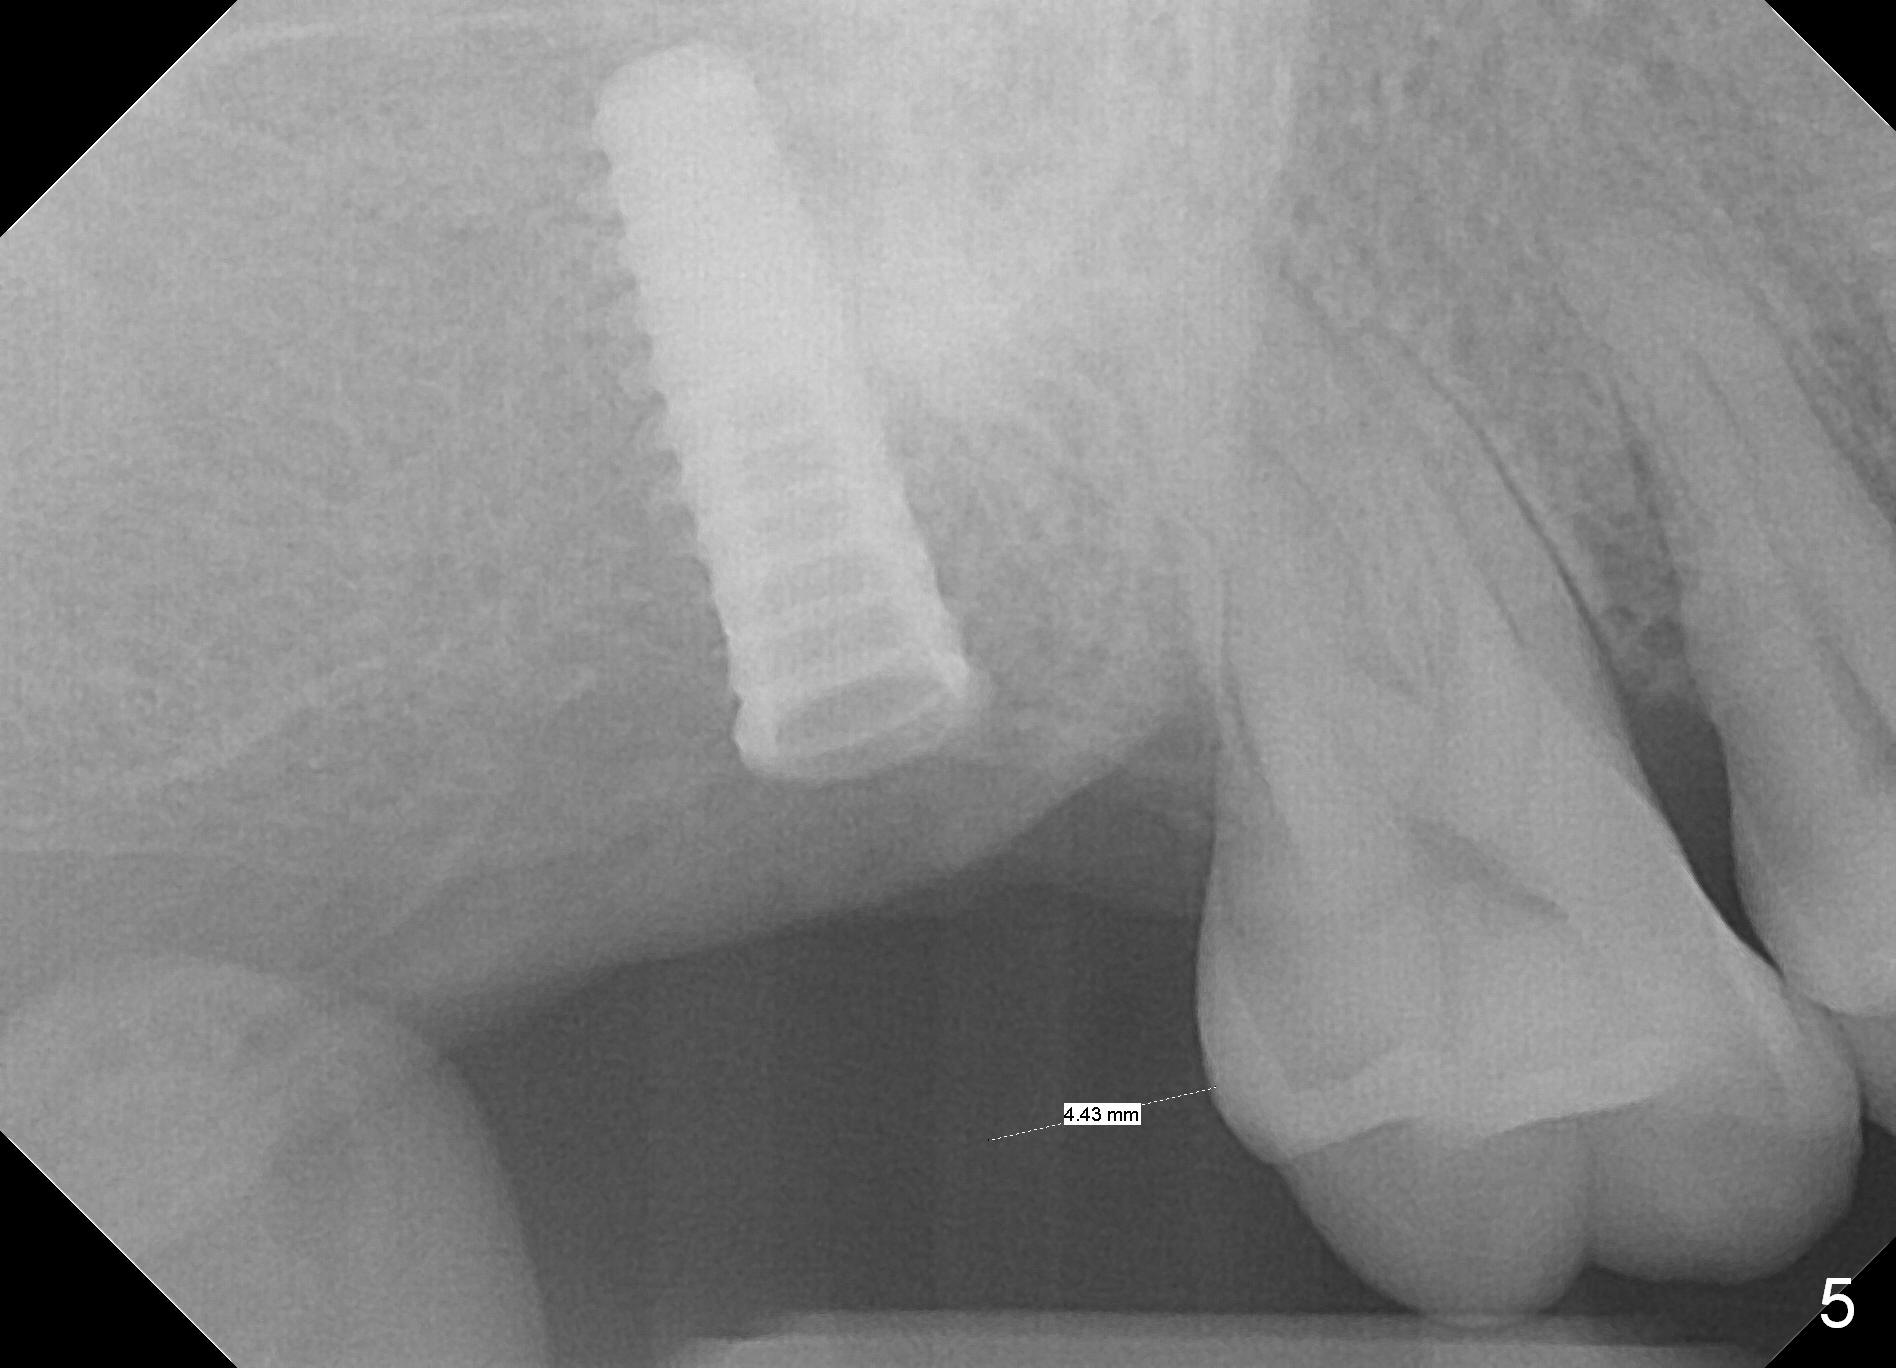

The edentulous ridge at the site of #2 is wide. Magic split is used to gain access, test bone density and start osteotomy for 9 mm (gingival level). A 1.6 mm drill is used to extend the osteotomy for depth of 13 mm. The osteotomy position and trajectory is confirmed with a parallel pin (Fig.1), which is ideal. The remaining osteotomy is finished with Magic Expanders from 3 to 4.3 mm for 15 mm. The trajectory is confirmed again with insertion of a 4.5x11 mm dummy implant at the depth of 15 mm (Fig.2). When a definitive IBS implant (5x13 mm) is placed with insertion torque >45 Ncm, the distal coronal end is not subcrestal (Fig.3-5). As the implant is placed deeper, it started to lose primary stability. When a pair abutment is placed, it keeps turning. Finally a healing abutment (6x3 mm) is placed unstable. In brief, taking several X-ray films help control osteotomy and implant position and trajectory. The implant is unstable 7 months postop (Fig.6). With local anesthesia, the implant is placed deeper by 1 mm with apparent increase in torque and a 6x4 healing abutment placed. The implant is stable 11 months postop. With 5.5x4(4) mm abutment placed, impression is taken. PA and BW will be taken after cementation of the crown. There is no bone loss 9 months post cementation (Fig.7). Return to Upper Molar Immediate Implant, 18-20, 29,30 Xin Wei, DDS, PhD, MS 1st edition 01/09/2017, last revision 08/15/2021